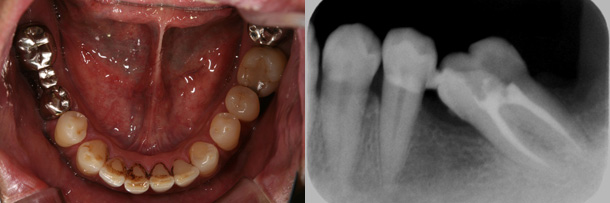

症例:傾斜した大臼歯の歯並びを改善し、ブリッジを装着することで咬み合わせを改善

主訴:奥歯が咬みにくい

診断:左側下顎第二大臼歯の近心傾斜

年齢:56歳

装置:下顎部分的ブラケット装置

治療期間:8か月

抜歯:なし

費用:50,000円+税

矯正前

矯正後